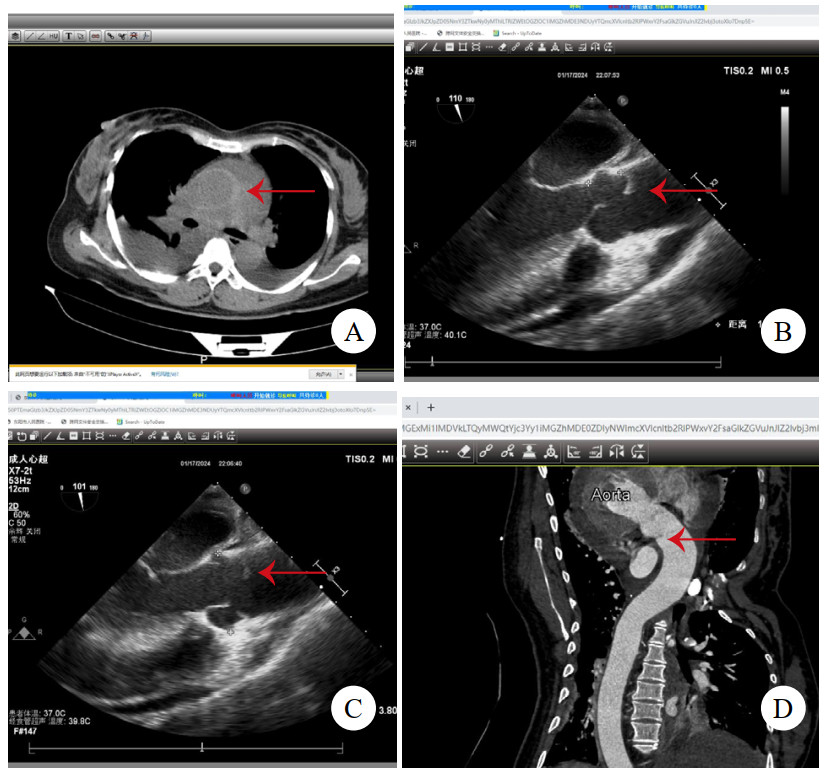

病例2,男,47岁,因“突发背痛伴胸闷1 h”入院。查心电图提示下壁导联ST段抬高0.1 mv,TTE提示节段性室壁运动异常,升主动脉及窦内径增宽,肌钙蛋白阴性,考虑“急性心肌梗死”。行急诊冠脉造影术,见冠状动脉通畅,加行主动脉造影见根部后壁斜行龛影(图 2A)。予查主动脉CTA,见主动脉根部左冠状动脉开口上方条状影(图 2B),该处主动脉直径为44 mm,升主动脉周围少量心包积血(图 2C),提示LIT。建议急诊开胸手术,患方自行至外院行升主动脉置换术,术中所见符合LIT,术后2个月至本院复查TTE,见升主动脉人工血管通畅(图 2D),无室壁运动异常。后门诊随访5年,情况平稳。

| 注:A为主动脉造影,箭头示根部后壁斜行龛影;B为主动脉CTA,箭头示左冠状动脉开口上方条状影;C为箭头示升主动脉周围少量心包积血;D为TTE见升主动脉人工血管通畅 图 2 例2患者主动脉根部造影、术前CT及术后TTE影像 |